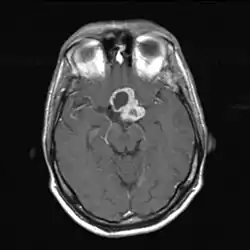

![]() КТ головы. Краниофарингиома находится в центре изображения | |

Диагностика основана на применении методов медицинской визуализации, заподозрить заболевание можно при рентгенографии черепа, подтверждается диагноз при компьютерной томографии или МРТ.

Магнитно-резонансная томография

Магнитно-резонансная томография (МРТ) даёт возможность определить точные размеры краниофарингиом, соотношение их узловой и кистозной частей, размеры и локализацию. Также МРТ даёт представление о состоянии желудочковой системы, наличии или отсутствии гидроцефалии, топографо-анатомическом взаимоотношении опухоли и дна III желудочка[32].

Сигнал от данного новообразования вариабелен[35]. В большинстве случаев кистозный компонент имеет гипоинтенсивный сигнал в режиме Т1 и гиперинтенсивный — в режиме Т2. При наличии высокой концентрации белка, продуктов распада крови, холестерина сигнал от кистозной жидкости может существенно меняться[36]. Это проявляется в повышении интенсивности сигнала. Данная особенность является высокоспецифичной именно для краниофарингиом. В режиме Т2 яркость сигнала может варьировать от гипер- до изоинтенсивного[32].

Солидная часть краниофарингиом в большинстве случаев не отличается по интенсивности сигнала от вещества мозга. При введении контрастных препаратов плотность сигнала усиливается[32].

При эндоселлярных краниофарингиомах размеры турецкого седла увеличены. Распространяясь вверх, новообразование заполняет область хиазмальных цистерн, в той или иной степени поддавливает дно III желудочка. Супраселлярная часть краниофарингиом чаще кистозная. Кисты могут распространяться на основание передней черепной ямки, перивентрикулярно или определяться внутри узловой части опухоли. Краниофарингиома чаще всего хорошо отграничена от прилежащего мозгового вещества[32].